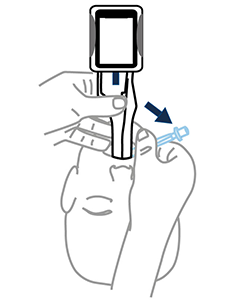

Center vocal cords

Push ETT

Twist Airtraq to center vocal cords

Corkscrew ETT if needed